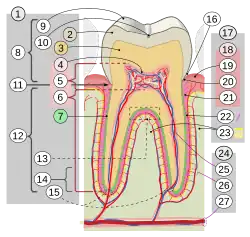

1. Zahn 2. Zahnschmelz 3. Dentin (Zahnbein) 4. Pulpencavum mit Pulpa 5. Kronenpulpa 6. Wurzelpulpa 7. Wurzelzement 8. Zahnkrone 9. Höcker 10. Fissur 11. Zahnhals 12. Zahnwurzel 13. Bifurkation 14. Wurzelspitze 15. Foramen apicale 16. Sulcus gingivae 17. Zahnhalteapparat 18. Zahnfleisch: 19. oral oder vestibulär 20. marginal 21. alveolar 22. Wurzelhaut mit Sharpey-Fasern 23. Alveolarknochen (Die feine gelbe Linie ist die Lamina dura). 24. Gefäße und Nerven: 25. Pulpa 26. Parodontium 27. Canalis mandibulae.

Jeder (echte) Zahn besteht aus der Zahnkrone (Corona dentis), dem Zahnhals (Cervix dentis, seltener: Collum dentis) und der Zahnwurzel (Radix dentis) und ist aus mehreren Schichten aufgebaut. Bei einem gesunden Zahn sieht man nur den Zahnschmelz, der wie eine Glasur das innen liegende Zahnbein (Dentin) bedeckt. Das Dentin wiederum umschließt das Zahnmark (Pulpa). Die Wurzel wird bis zum Zahnhals von Wurzelzement (Cementum) und Wurzelhaut umschlossen.